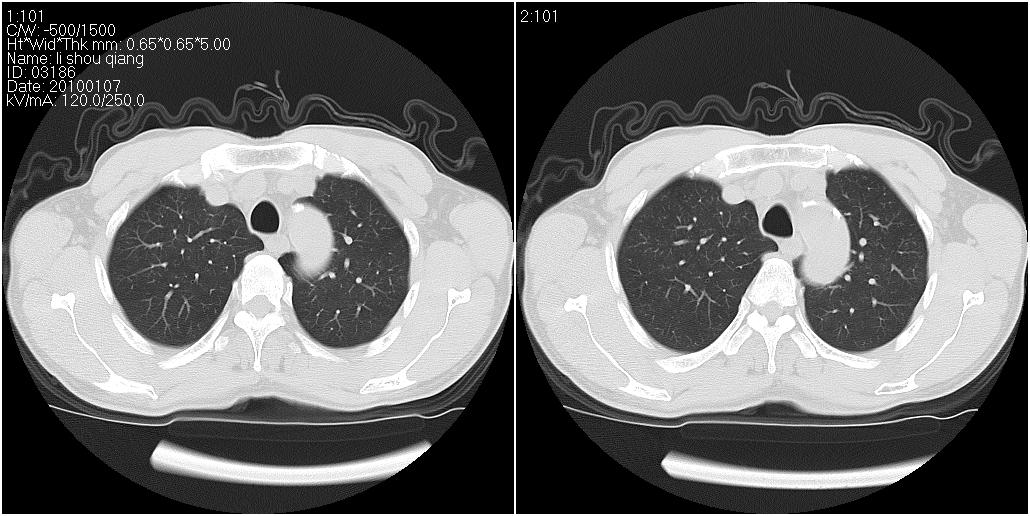

标题: CT24038:男性,58岁。主因咳嗽带血性CT检查。 [打印本页]

标题: CT24038:男性,58岁。主因咳嗽带血性CT检查。

右肺中叶外侧段见一不规则的软组织肿块,边缘可见毛刺,并见厚壁空洞,与胸膜分界欠清。另左下肺见多个小囊状扩张区

右肺中叶外侧段可见团块影,外形不规则,内见空泡征。左下肺见蜂窝状低密度透亮影,部分层面主动脉旁瘤样突出。考虑右肺中叶外围型肺癌可能性大,左下肺支气管扩张,主动脉弓瘤样突出。

1、右肺中叶周围型肺癌(内空泡)。

2、左肺下叶支扩,不除外合并肺囊肿。

3、建议冠状位重建除外主动脉弓息室样动脉瘤。